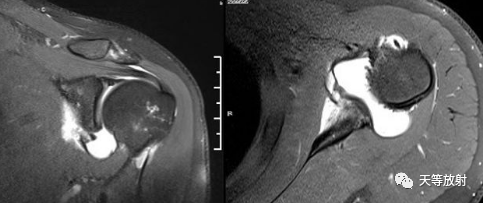

Bankart损伤的MR表现

-

三角形变钝

盂唇撕裂:关节盂唇软骨与盂缘可见线状高信号影并连续到关节面下

盂唇完全消失或盂唇明显移位

若盂唇损伤合并关节盂骨质损伤,称为骨性Bankart病变

骨性Bankart病变

MR间接关节造影1.5T轴位T1W脂肪抑制(TR=460s,TE=90s)